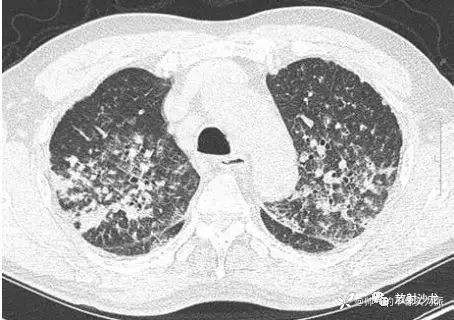

胸部平片见图1。胸部CT扫描显示多发结节、双侧气腔实变和磨玻璃征(图2),多发结节都分布在淋巴组织周围。腹部CT平扫显示胰头处有一个直径2 cm 的低密度团块阴影(图3)。对患者行气管镜检查以除外恶性疾病或结核,术中未见支气管内病变。对支气管镜获取的样本进行了细胞学检测、抗酸染色和TB聚合酶链反应,结果均为阴性;支气管肺泡灌洗液培养也为阴性。多重聚合酶联反应未检测到A 型和B 型流感病毒、1~3型副流感病毒、呼吸道合胞病毒、腺病毒、鼻病毒以及间质肺病毒。

图2 胸部CT示多发结节、双侧气腔实变以及磨玻璃征